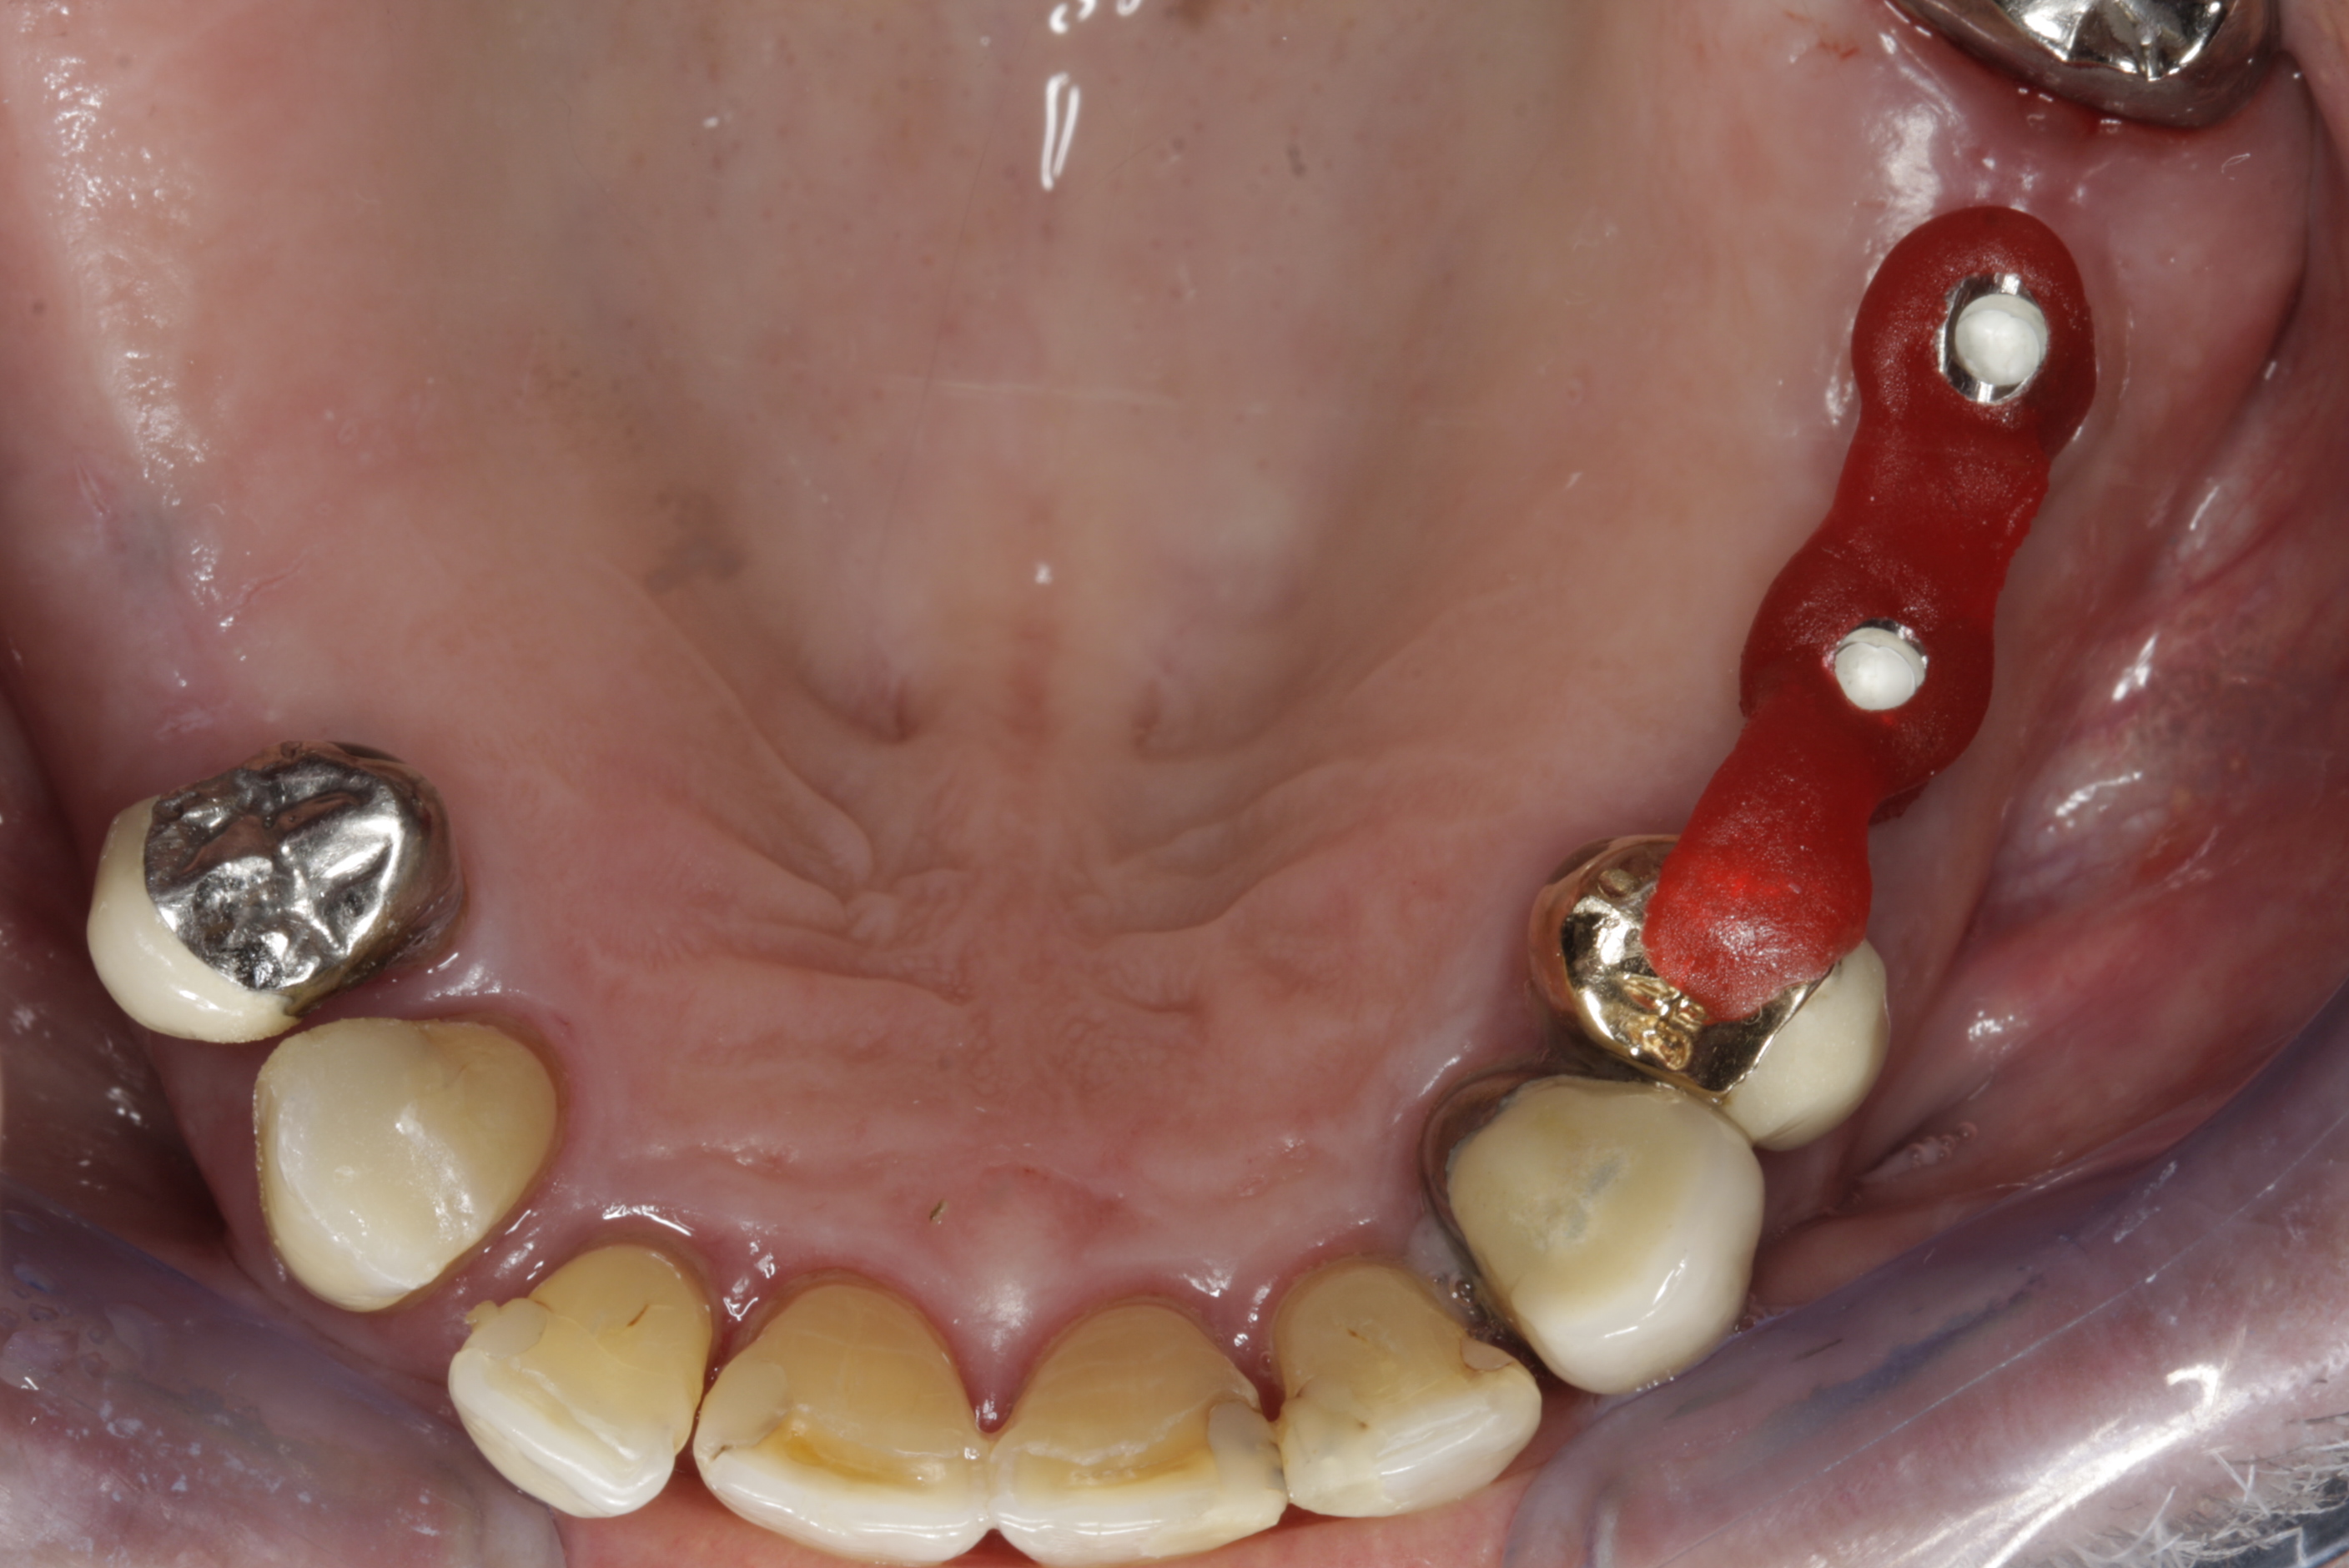

Během let může postupnou ztrátou zubů zůstat v ústech omezený počet zubů, které umožňují držení zubních náhrad.

V důsledku přetížení zbylých zubů např. houpavými pohyb snímacích náhrad dochází k uvolnění těchto zubů a držení můstků a protéz je tak velmi těžké. V těchto případech můžeme pomocí implantátů zvýšit počet pilířů a tím zabránit přetěžování a ztrátě zbylých zubů

Bezzubá čelist je hlavní indikací pro ošetření pomocí implantátů. Zejména celkové zubní náhrady v dolní čelisti mají velice nízkou stabilitu a držení díky velkému úbytku kosti.

S pomocí zubních implantátů můžeme díky různým kotevním systémům (třmeny, kulové hlavy, Locatory) zajistit stabilitu a držení protézy nebo při použití většího počtu implantátů zhotovit pevné náhrady – můstky nalepené nebo našroubované na pevno na implantáty.

S těmito typy náhrad můžeme dosáhnout perfektní funkci, výbornou estetiku, fonetiku a současně zajistit u pacienta možnost dobré hygienickou péče a čištění, která je pro životnost implantátů velice důležitá.